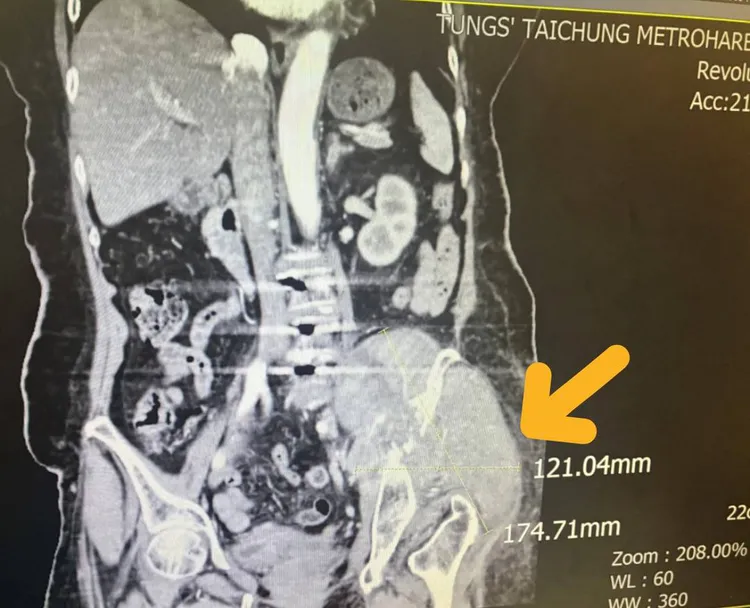

黃色箭頭即為患者左側骨盆骶骨處出現異常12.1公分x17.4公分左右大型腫瘤細胞。童綜合醫院提供